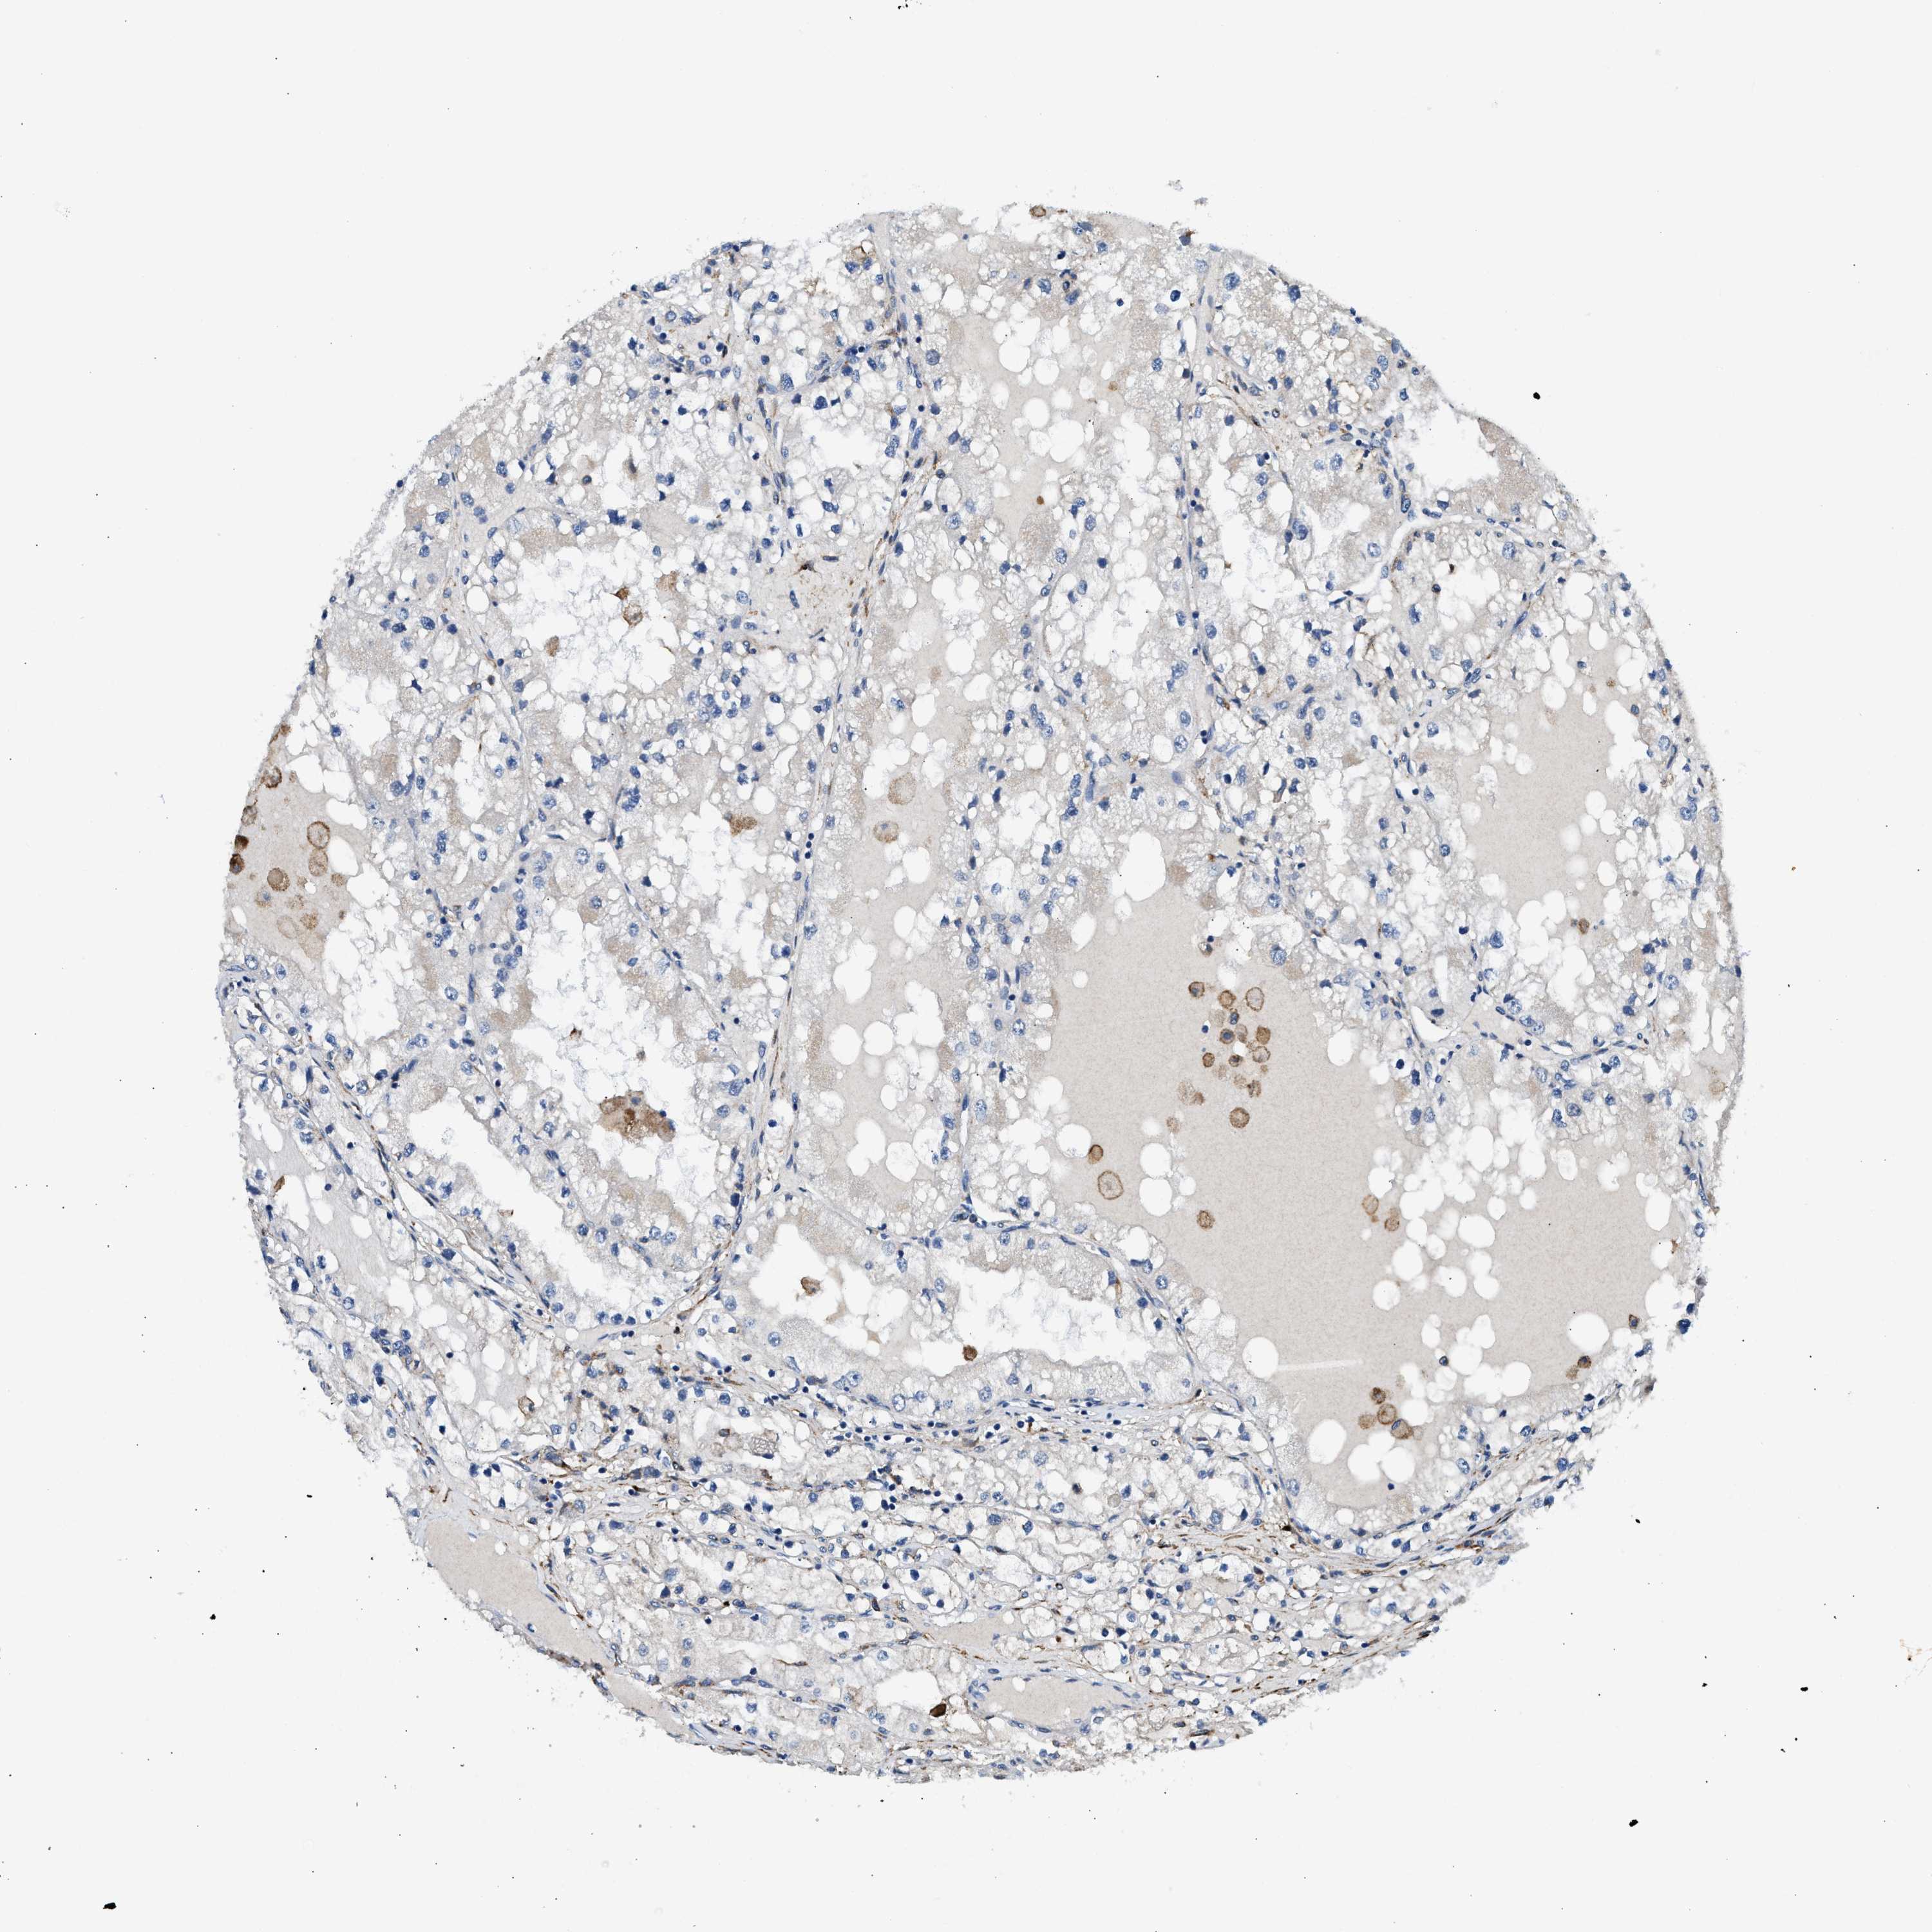

KIDNEY RENAL PAPILLARY CELL CARCINOMA (TCGA) - Interactive survival scatter ploti

The Survival Scatter plot shows the clinical status (i.e. dead or alive) for all individuals in the patient cohort, based on the same data that underlies the corresponding Kaplan-Meier plots. Patients that are alive at last time for follow-up are shown in blue and patients who have died during the study are shown in red.

The x-axis shows the expression levels (FPKM) of the investigated gene in the tumor tissue at the time of diagnosis. The y-axis shows the follow-up time after diagnosis (years). Both axes are complimented with kernel density curves demonstrating the data density over the axes. The top density plot shows the expression levels (FPKM) distribution among dead (red) and alive patients (blue). The right density plot shows the data density of the survived years of dead patients with high and low expression levels respectively, stratified using the cutoff indicated by the vertical dashed line through the Survival Scatter plot. This cutoff is automatically defined based on the FPKM cutoff that minimizes the p-score. The cutoff can be changed by dragging the vertical line or by entering a cutoff value in the square labeled "Current cut-off".

Under the Survival Scatter plot the p-score landscape (black curve; left axis) is shown together with dead median separation (red curve; right axis). Dead median separation is the difference in median mRNA expression between patients who have died with high and low expression, respectively. It is calculated as follows: median FPKM expression of dead patients with high expression - median FPKM expression of dead patients with low expression. This is intended to aid the user in visually exploring custom cutoffs and the associated p-scores and dead median separation.

Individual patient data is displayed and can be filtered by clicking on one or more of the category buttons on the top of the page. Categories describing expression level and patient information include: high, low, alive, dead, female, male and tumor stages. The scale of the x-axis can be toggled between linear and log-scale by clicking on the "x log" button. Mouse-over function shows TCGA ID, patient information and mRNA expression (FPKM) for each patient.

& Survival analysisi

Kaplan-Meier plots summarize results from analysis of correlation between mRNA expression level and patient survival. Patients were divided based on level of expression into one of the two groups "low" (under cut off) or "high" (over cut off). X-axis shows time for survival (years) and y-axis shows the probability of survival, where 1.0 corresponds to 100 percent.

LRP1 is not prognostic in Kidney Renal Papillary Cell Carcinoma (TCGA)